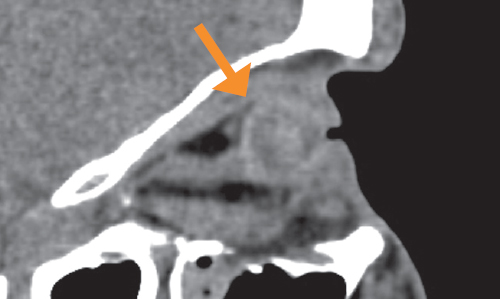

Fig. 8. MSCT of the orbit, axial section, bone reconstruction regimen. The state after enucleation of the right globe because of retinoblastoma without formation of a supporting-motor stump and installation of an endoprosthesis. In the anterior parts of the right orbit, an external cosmetic prosthesis is visualized with its prolapse into the orbital cavity, as well as the optic nerve stump and extraocular muscles

Рис. 8. МСКТ орбиты, аксиальный срез, режим костной реконструкции. Состояние после энуклеации правого глазного яблока по поводу ретинобластомы без формирования ОДК и установки эндопротеза. В передних отделах правой орбиты визуализируется наружный косметический протез с пролабированием его в полость орбиты (КТ-признаки энофтальма, стрелка), а также культя зрительного нерва и глазодвигательные мышцы